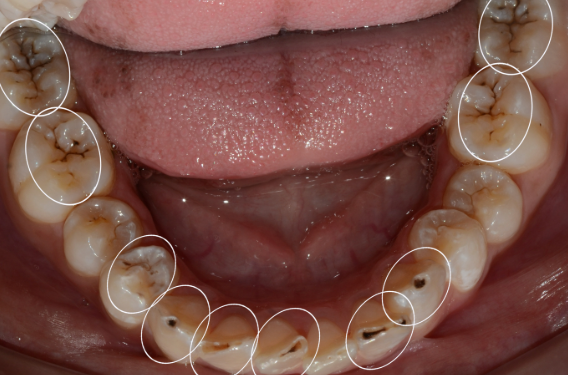

아랫니 충치의 또 다른 특징은

한 곳에만 생기지 않는다는 점입니다.

치아 사이사이에 숨어있는 인접면 충치가

동시다발적으로 발생하는 경우가 많습니다.

인접면 충치는

육안으로는 거의 보이지 않습니다.

겉으로는 멀쩡해 보이지만 엑스레이를 찍어보면 여러 치아에 충치가 동시에 진행되고 있는 것을 발견하게 됩니다.

아랫니는 특히 침샘 근처에 위치해 있어

세균의 번식이 활발하고,

칫솔질이 상대적으로 어려운 부위이기 때문에

여러 치아에 동시에 충치가 발생할 확률이

높습니다.